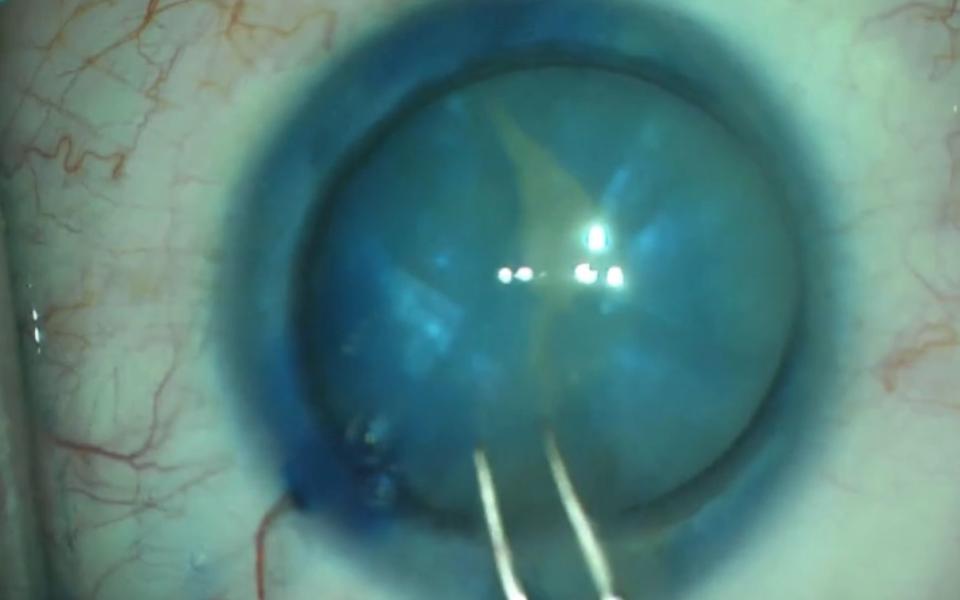

The Argentinan Flag sign more commonly occurs in patients with mature nuclear sclerosis. The anterior capsule is stained with trypan blue (Vison Blue). When the capsule is decompressed with a 25G